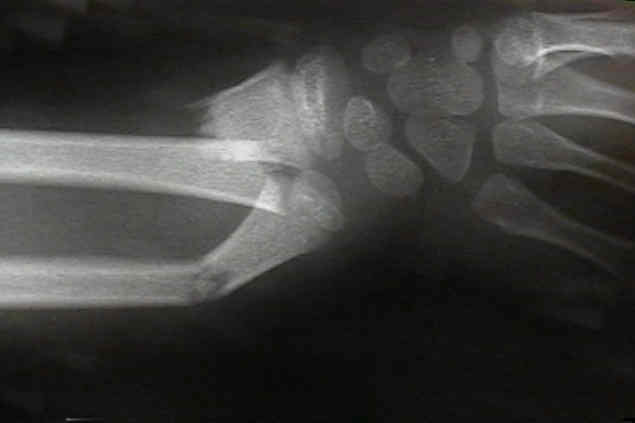

bayonette apposition

- generally bayonette opposition will require operative reduction (either closed with a Kapandji K wire levering technique or in some situations, an open reduction and fixation with K wires will be required);

- historically, overriding of a both bones forearm fracture was acceptable if...

- there was no deviation of radius and ulna toward each other;

- there was no encroachment of the interosseous space;